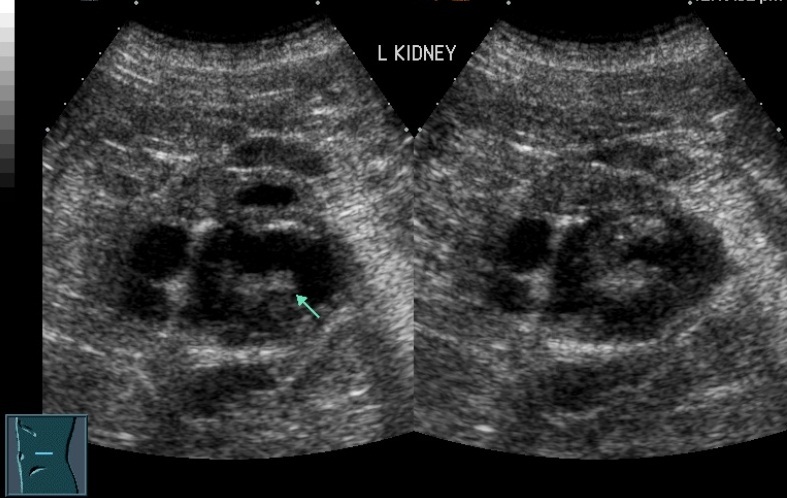

19F Hypertensive

kypokalaemia

elevated aldosterone

Juxtaglomerular Tumor (Reninoma)

Reninoma is a tumour of the cells of the juxtaglomerular apparatus that produces excessive amounts of renin, resulting in a secondary form of hyperaldosteronism, manifesting clinically with hypertension (HT) and hypokalaemia1. This renal tumour is predominant in females, with a peak incidence between the second and third decade of life and, although uncommon, it is a treatable cause of HT2. It should be suspected in any patient with refractory HT associated with hypokalaemia and high levels of aldosterone.

We present the first case of reninoma reported in Argentina in a young woman with refractory HT and hypokalaemia.

In 1967, Robertson et al.6 reported the first renin-producing tumour. Kihara et al. later called them “juxtaglomerular cell tumours”7. These tumours are very uncommon, with their incidence peaking between the second and third decade of life and they are predominantly found in females, originating in the myoendocrine cells of the renal juxtaglomerular apparatus, although the production of renin by different tumours has also been demonstrated, such as Wilms tumours, carcinoid tumours, renal oncocytoma and renal cell carcinoma8,9. In accordance with the presence or absence of symptoms, JCT may occur as: a “typical” variant in the majority of cases and manifests with HT, hypokalaemia, high plasma renin and secondary hyperaldosteronism; an “atypical” variant, in which HT is not accompanied by hypokalaemia; and a third “non-functioning” variant, which occurs without HT and with normal levels of potassium10,11.

Plasma renin activity (PRA) and plasma aldosterone (PA)